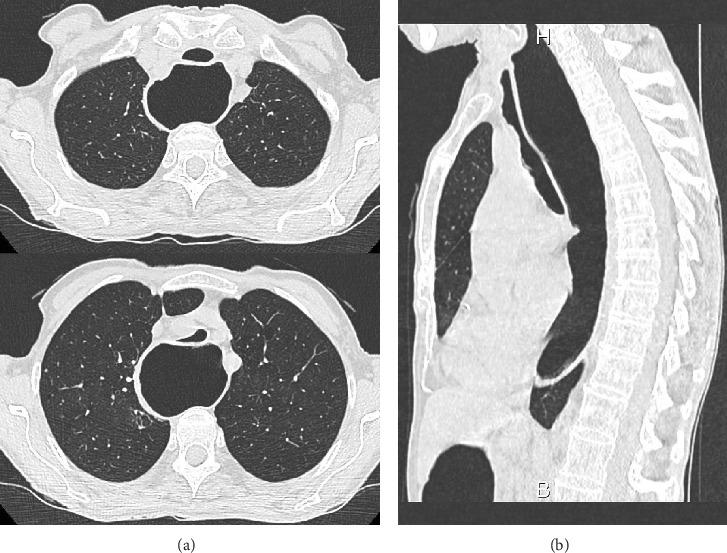

We report the case of an 80-year-old woman who presented one episode of cardiopulmonary arrest and two episodes of acute airway obstruction. We found in this patient the presence of tracheomalacia caused by megaesophagus compression secondary to achalasia probably responsible for episodes of acute airway obstruction and cardiopulmonary arrest.

我们报告了一名80岁女性的病例,该患者出现了一次心肺骤停和两次急性气道梗阻。我们发现该患者存在由贲门失弛缓症继发的巨食管压迫导致的气管软化,这可能是急性气道梗阻和心肺骤停发作的原因。